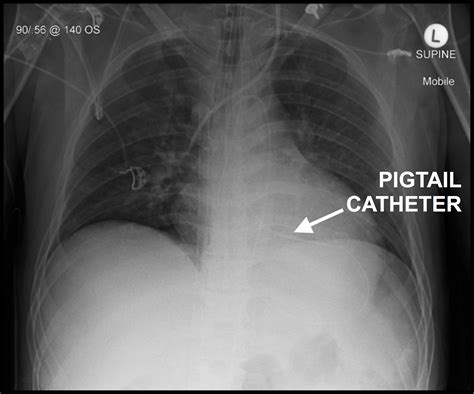

In the realm of medical procedures, the insertion and management of a Pigtail Chest Tube is a critical skill for healthcare professionals. This procedure is essential for draining fluid or air from the pleural space, which can accumulate due to various medical conditions such as pneumothorax, pleural effusion, or empyema. Understanding the intricacies of this procedure, from preparation to post-insertion care, is vital for ensuring patient safety and effective treatment.

A Pigtail Chest Tube is a small, flexible tube with a coiled end that resembles a pigtail. This design allows for easier insertion and reduced trauma to the patient compared to traditional chest tubes. The tube is typically inserted using a Seldinger technique, which involves the use of a guidewire to facilitate placement. The primary function of a Pigtail Chest Tube is to drain excess fluid or air from the pleural space, thereby relieving pressure and promoting healing.